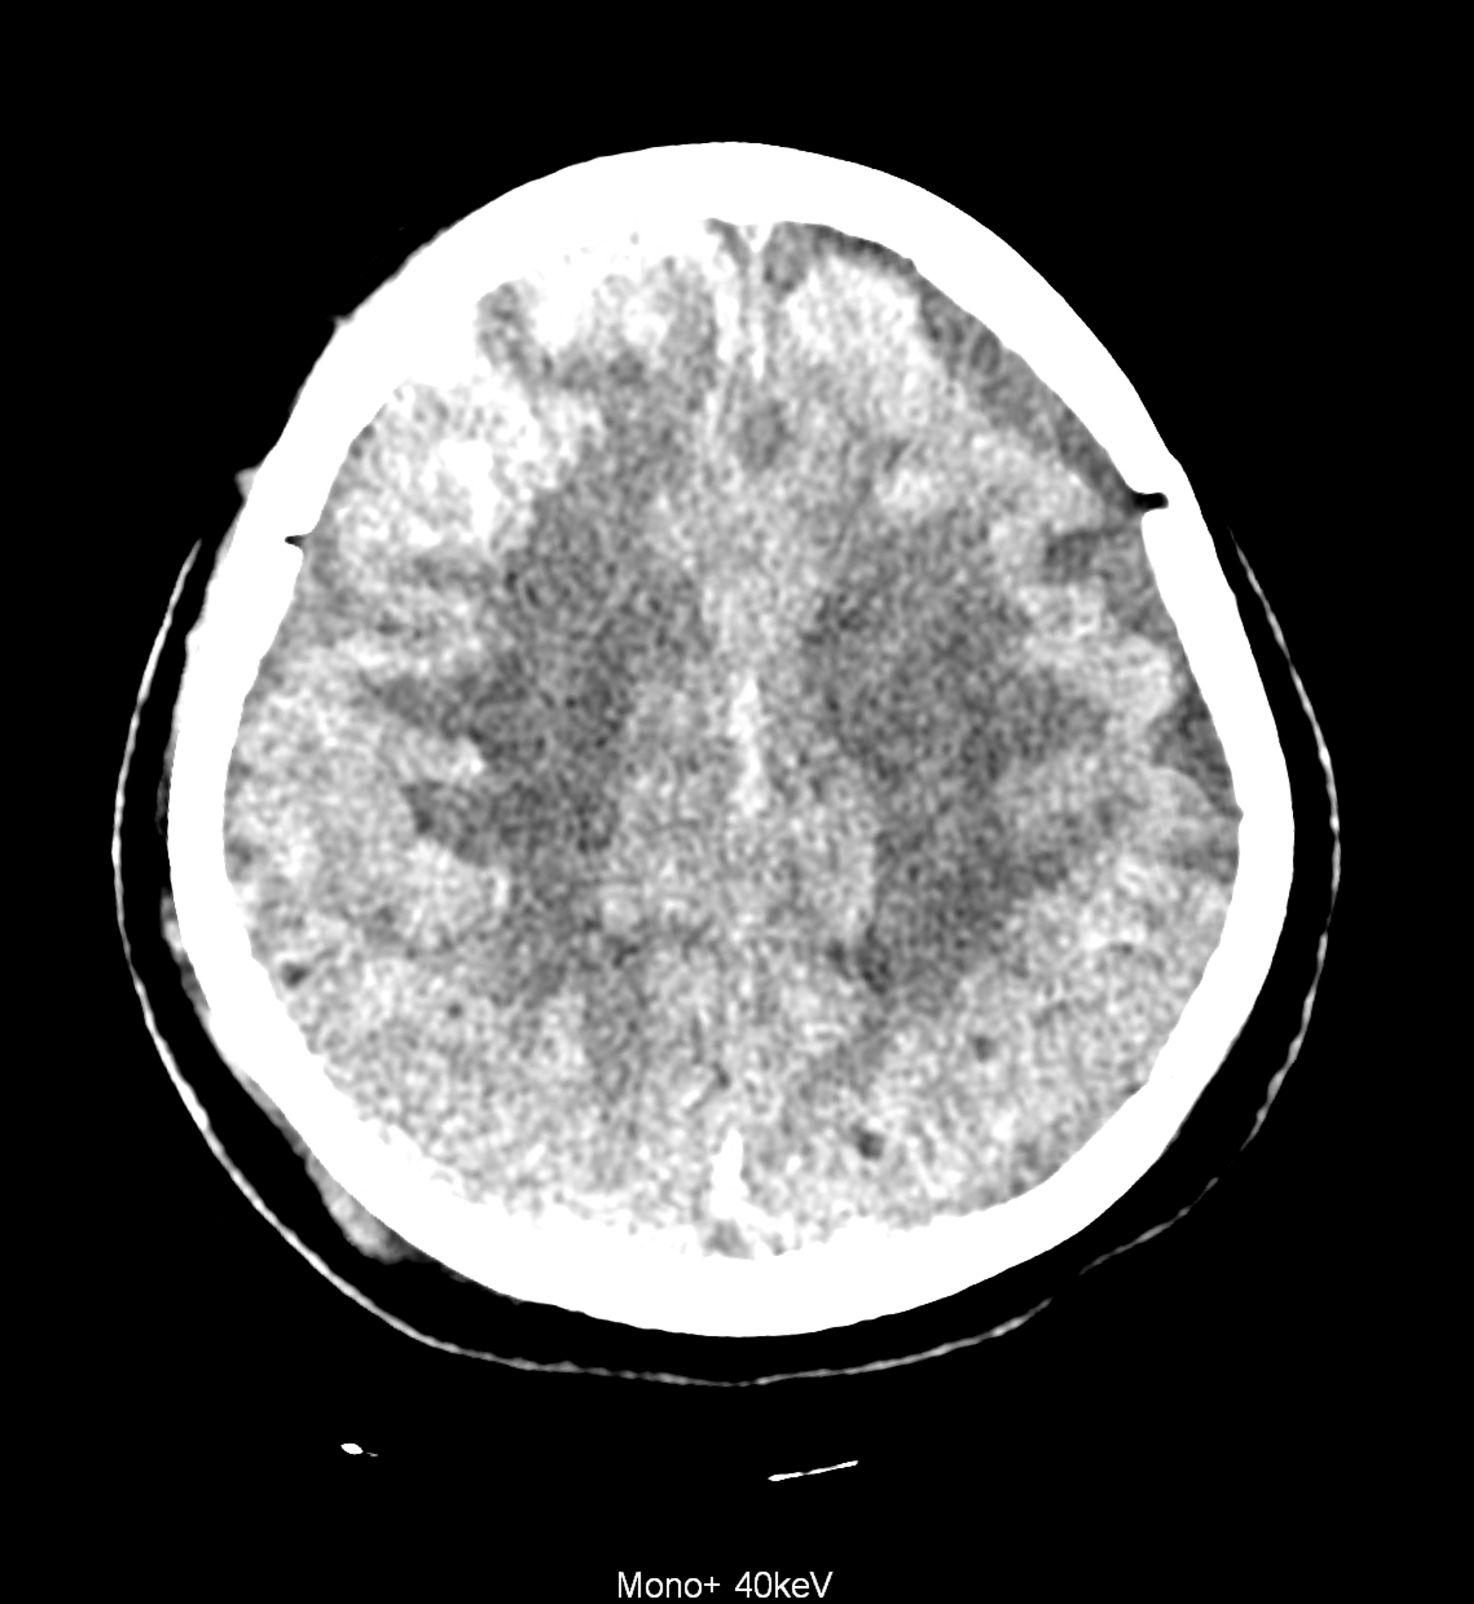

An example of the use of spectral imaging in complex brain injury, where contusions, diffuse axonal injury, subarachnoid hemorrhage, subdural hemorrhage, and blood in the ventricular system are present.

comparison of the images with the energies of monoenergetic reconstructions 40 keV, 67 keV (standard conventional reconstruction), 190 keV and virtual non contrast (VNC)

Bleeding is characterized by different absorption characteristics than healthy brain tissue (both gray and white matter) and cerebrospinal fluid. Due to the higher proportion of proteins with amino acids with disulfide bonds, the signal intensity increases at higher energies, making it possible to use monoenergetic imaging at energies above 140 keV, and/or virtual non-contrast. The hemorrhage then becomes more hyperdense, while the rest of the brain tissue acquires a uniform low signal. In addition to bleeding, areas of extracellular fluid of vasogenic origin are also imaged, i.e., in areas around contusion-type brain tissue injuries.